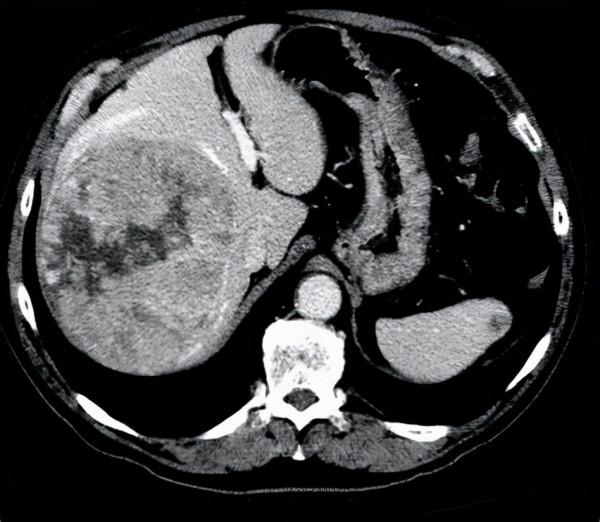

三、肚子越來越大:肝臟問題。

有的患者平時感覺挺健康的,不過在一段時間內,總感覺肚子越來越大了,肚子裡面的水可能變多。

這其實是一種非常不容易發現的水腫:腹水。

S如果出現了腹水,很多時候都是由肝臟疾病所導致的,所以腹水常常也都是很難治療的。

一般來說肝臟淋巴迴圈受阻或者門脈高壓以及低白蛋白血癥他們共同作用都會導致腹水的生成,所以治療起來非常困難。

而且如果因為肝臟疾病出現了全身的水腫,這並不代表肝臟本身的問題,同時也表現出全身營養不良。

肚子太大真的不是什麼好事,萬一是腹水就麻煩了。